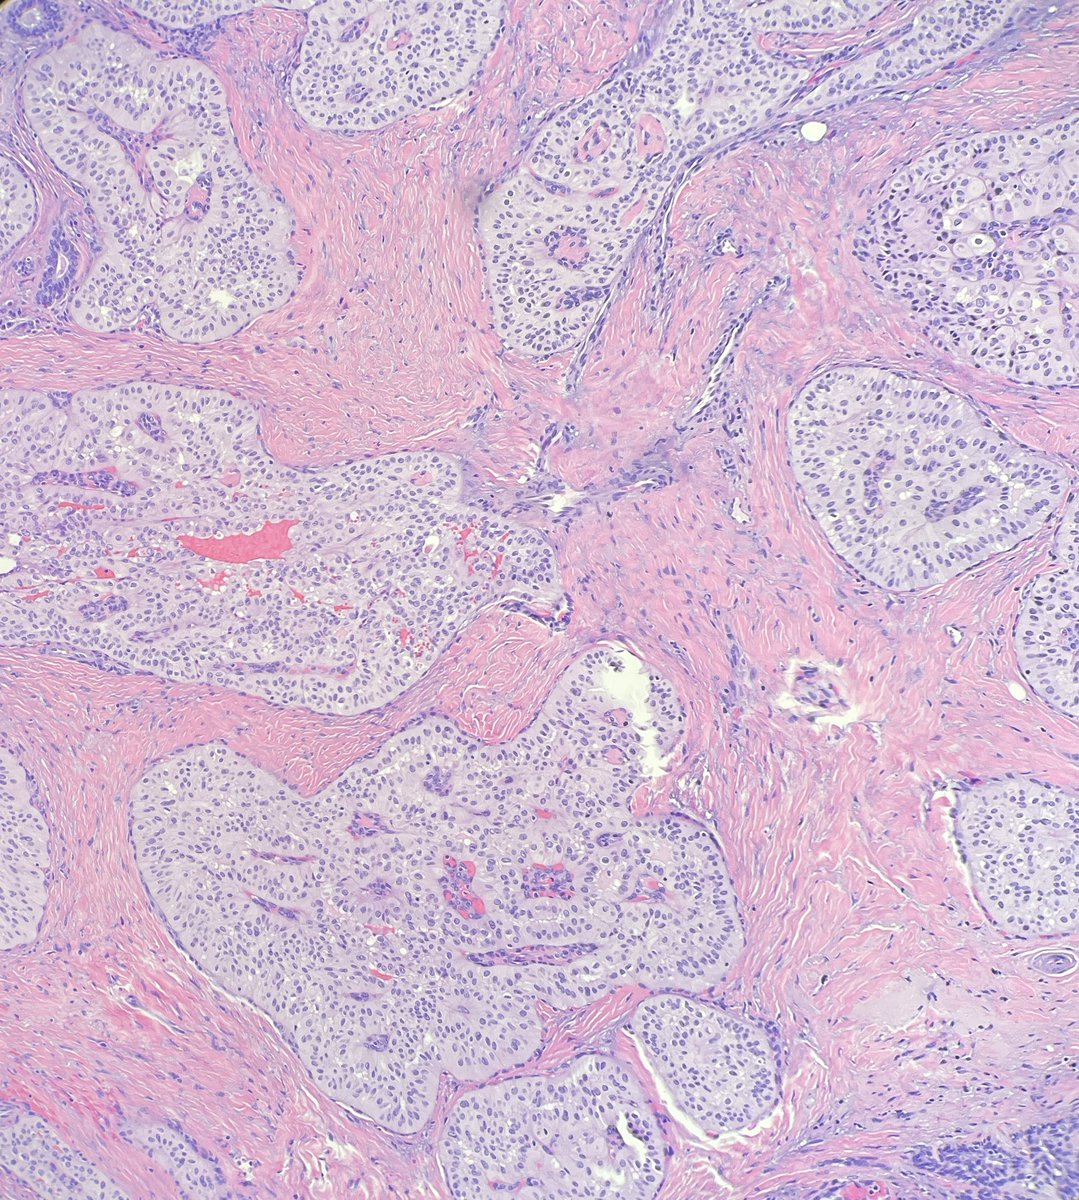

1/ #breastpath lovers, have you heard about this new entity of "serous carcinoma-like" breast carcinoma? 😉 #pathology #IHCpath- the IHCs showed negativity for ER, PR, HER2, GATA3, Sox10

1/ #breastpath lovers, have you heard about this new entity of "serous carcinoma-like" breast carcinoma? 😉

#pathology #IHCpath- the IHCs showed negativity for ER, PR, HER2, GATA3, Sox10